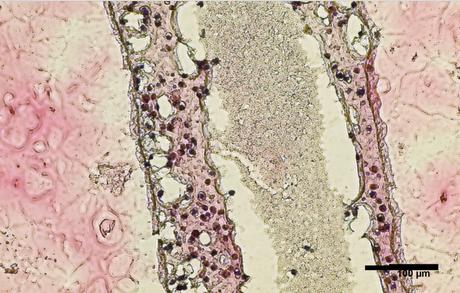

Imprimer et spécialiser des cellules de remplacement : ici, les chercheurs ont effectué une biopsie pour collecter des cellules souches des testicules d’un patient atteint d’azoospermie non obstructive. Les cellules ont été cultivées et imprimées en 3D dans ne boîte de Pétri dans une structure tubulaire creuse qui ressemble aux tubes séminifères humains producteurs de sperme (visuel). L’expérience montre que :